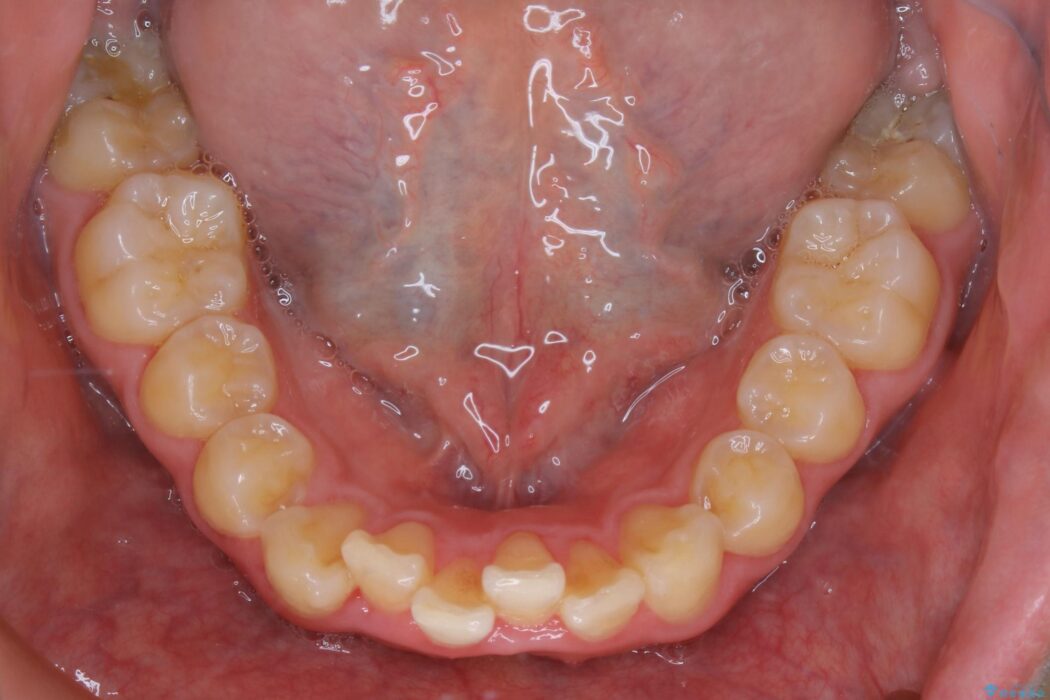

上の歯の出っ歯と下の歯のガタつきが気になるとご来院された患者様です。

出っ歯とガタつきの改善には抜歯が必要と診断し、上下左右第一小臼歯を抜歯することとしました。